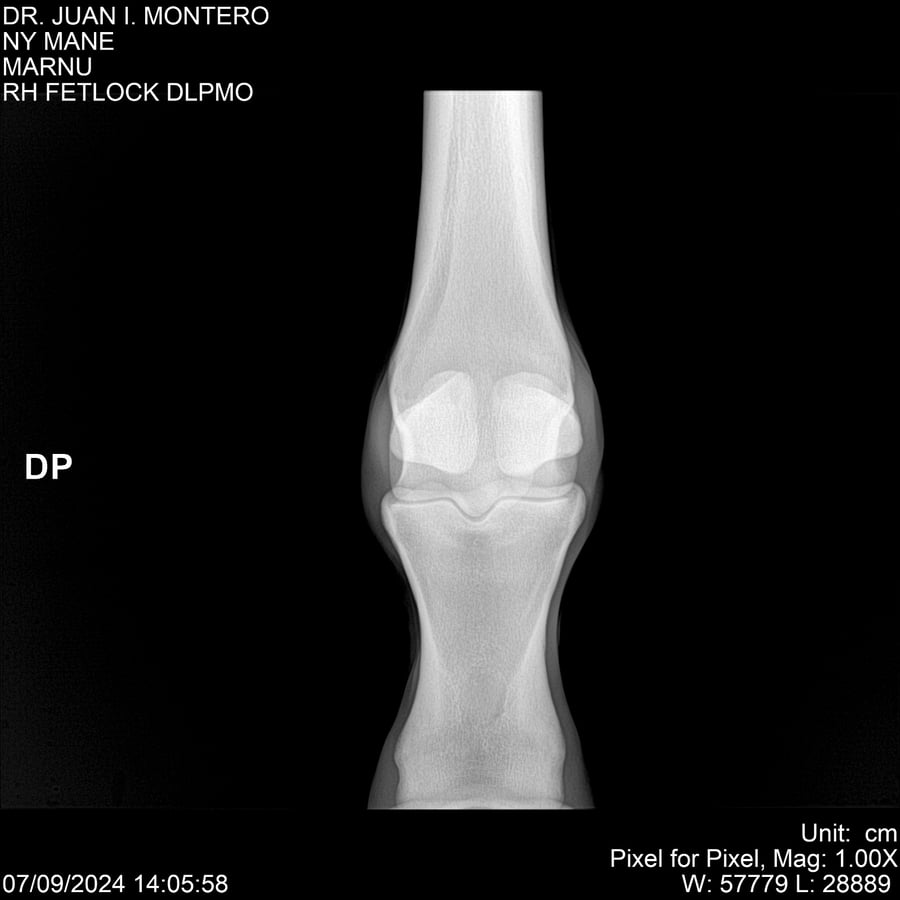

LOTE 20, NY MANE Lote Anterior Volver al remate Lote Siguiente Ficha Contacto Montevideo - Ficha del Lote Identificador: #282520 Categoría: Yeguarizos 76 Visualizaciones ClicData Contacto Empresa: Abelenda N. R., Walter Hugo Nombre*: Teléfono* : E-mail* : Mensaje Enviar Registrese gratis Este contenido Exclusivo está disponible sólo para usuarios registrados Ingresar